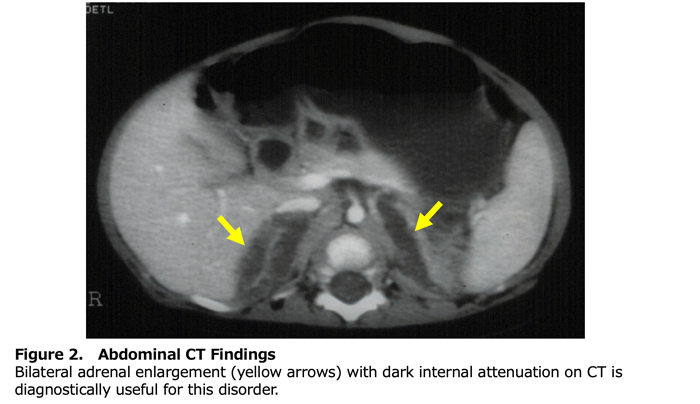

Blood tests and genetic testing are performed to diagnose this condition. When blood levels of adrenal and gonadal hormones are low and levels of hormones that stimulate the adrenal glands and gonads are high, this condition is suspected. Imaging tests may confirm fat accumulation in the adrenal glands (Figure 2). Genetic testing examines the STAR gene, but under the current Japanese healthcare system, it is not covered by insurance (out-of-pocket cost: 49,500 yen).